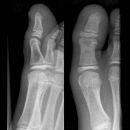

D1 Grundglied